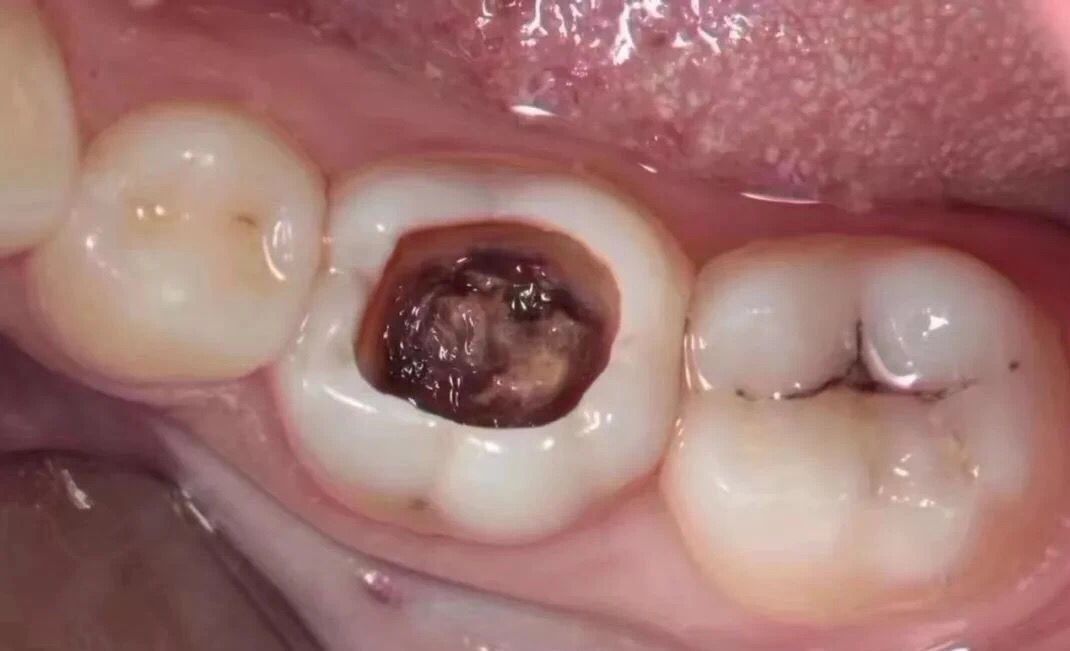

当您进食时,没法咬食物,您说:“还好,可以用另外一边牙齿咬。”

牙医告诫说:“病变已经破坏到了牙本质深层,牙齿有较深的龋洞,温度刺激,化学刺激以及食物进入龋洞时均引起疼痛,此时,及时做充填治疗的话还来得及保住牙髓。”